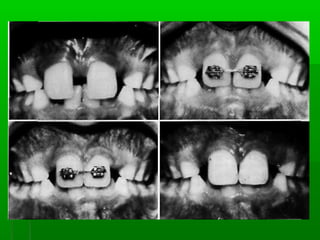

A small but unaesthetic diastema ( 2mm orA small but unaesthetic diastema ( 2mm or

less ) can be closed by tipping the centalless ) can be closed by tipping the cental

incisors together.incisors together.

 If diastema > 2mm can be reduced byIf diastema > 2mm can be reduced by

tipping the central incisors together withtipping the central incisors together with

RA.( 0r ) Fixed appliance.RA.( 0r ) Fixed appliance.

Types of applianceTypes of appliance

 Removable appliance ( Hawley'sRemovable appliance ( Hawley's

appliance)appliance)

Incorporating two finger springs distal to theIncorporating two finger springs distal to the

central incisorscentral incisors

Labial bowLabial bow

Adam's clasp or “ C “ claspAdam's clasp or “ C “ clasp

 Fixed orthodontic applianceFixed orthodontic appliance

 TreatmentTreatment  Beforemaxillary canine eruptedBefore maxillary canine erupted If diastema 2mm or lessIf diastema 2mm or less No treatment (close spontaneously )No treatment (close spontaneously ) A small but unaesthetic diastema ( 2mm orA small but unaesthetic diastema ( 2mm or less ) can be closed by tipping the centalless ) can be closed by tipping the cental incisors together.incisors together.

 If diastema> 2mm can be reduced byIf diastema > 2mm can be reduced by tipping the central incisors together withtipping the central incisors together with RA.( 0r ) Fixed appliance.RA.( 0r ) Fixed appliance.  Bodily movement by FA.Bodily movement by FA.

Types of applianceTypesof appliance  Removable appliance ( Hawley'sRemovable appliance ( Hawley's appliance)appliance) Incorporating two finger springs distal to theIncorporating two finger springs distal to the central incisorscentral incisors Labial bowLabial bow Adam's clasp or “ C “ claspAdam's clasp or “ C “ clasp